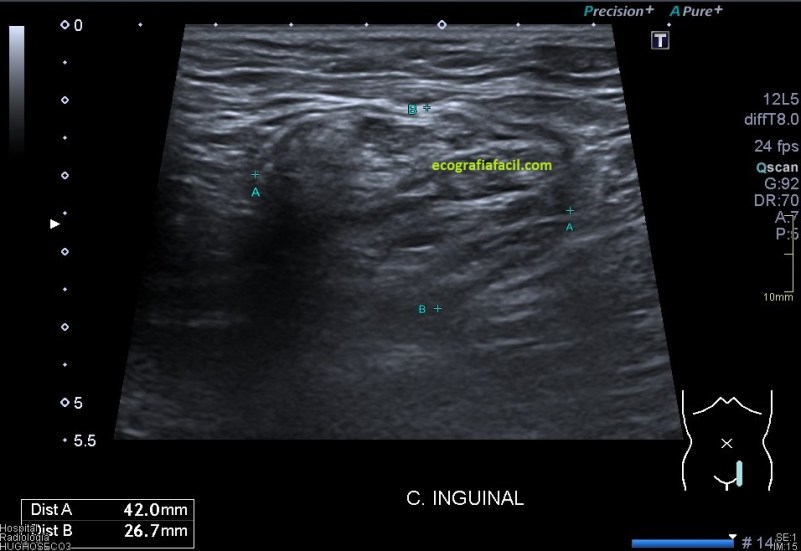

El paciente se presenta con una lesión tipo bulto en la región inguinal con una sospecha de su médico de familia de hernia inguinal. Al realizar este estudio, enseguida, el técnico que realiza la exploración se da cuenta que el patrón de comportamiento de la lesión no es la de una lesión herniaria aunque su aspecto pudiera parecerlo en un primer momento. Procede con el protocolo habitual de estudio para bultomas, localización, estudio, medida y vascularización, además, de maniobra de valsalva para descartar una hernia.

Así en esta imagen podemos ver que tienen criterio ultrasonográfico de hernia inguinal, más raro, pero posible, de lipoma, el problema para la primera opción es que con la maniobra de valsalva la lesión era inmóvil. Cuando estudias una lesión no solo es importante la semiología, también su comportamiento y la relación que tiene con los tejidos adyacentes.

Toca ahora después de la localización y estudio, las medidas que arrojaban una lesión bastante grande.

Se completa estudio con Ct ante las características de la lesión y la imagen que tenemos, muy llamativa, refrenda la presencia de una lesión en el canal inguinal que posee una gran calcificación.  En el CT se objetiva, imagen 7, una afectación ligeramente mayor a la estimada en el estudio ecográfico. La sospecha para la radióloga fue de lesión primaria de cordón inguinal compatible con Liposarcoma, a tenor de todos lo hallazgos en las dos pruebas, basándose principalmente en la heterogenicidad de la imagen, la calcificación y el comportamiento no compatible con hernia inguinal ni con la semiología típica del lipoma.